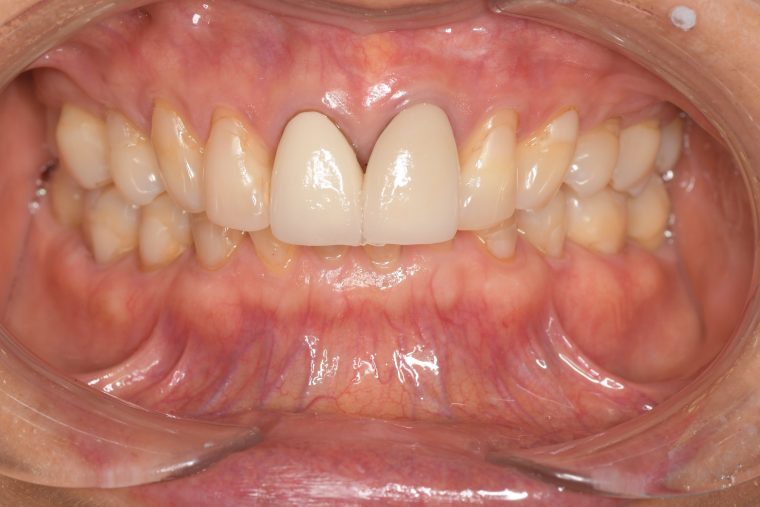

After

症例

担当者所見 左上は歯ぐきがかなり腫れていたが、歯石除去とホームケア(歯ブラシ、歯間ブラシSサイズ、ミクリンタフトブラシ)と抗生物質(軟膏)により腫れが落ち着いた。

それに加え、過度な力がかからないよう、ナイトガードを毎日使って頂くことと、日中の食いしばりにも気をつけてもらうようにした。

これは上の前歯を守るためのものでもあるので、必ず使用して頂いています。(上の前歯は神経がない為栄養が行き届かないので神経がある歯に比べ脆く根っこにヒビが入りやすい)

そして現在は定期検診で毎回異常がないか確認し、ホームケアではなかなか届かない歯周ポケット内のクリーニングを行っています。一度骨が溶けてしまっている為、歯周ポケットは残りますが、その後再発することは今のところなく、定期検診で今後もしっかり管理していきます。